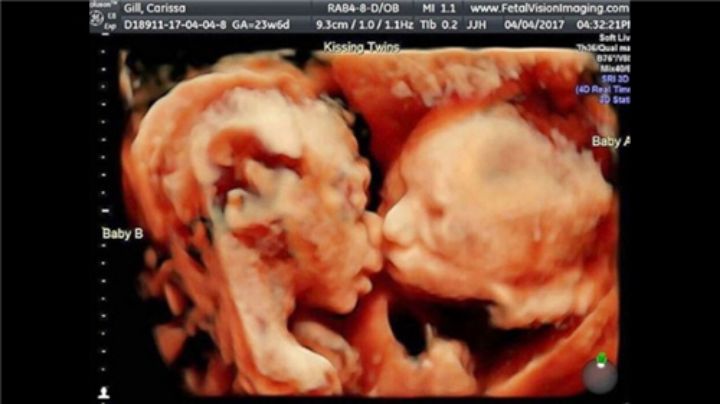

B超孕32周的双胞胎胎儿影像图▼: